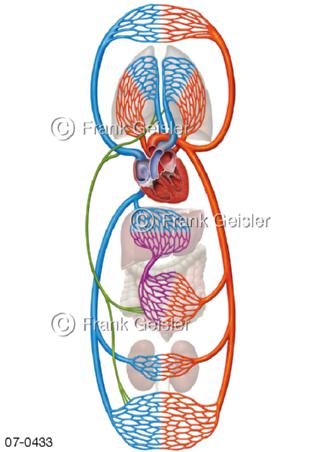

Bildergalerie Herz, Blutkreislauf

Bilder zu Herz, ein muskuläres Hohlorgan, das den menschlichen Körper durch rhythmische Kontraktionen mit Blut versorgt und dadurch die Durchblutung der Organe sichert, das Kreislaufsystem zeigt den Transport von arteriellem sowie venösem Blut durch das kardiovaskuläre System (Herz-Kreislauf-System), bestehend aus Blutgefäßen, Lymphgefäßen und dem Herz